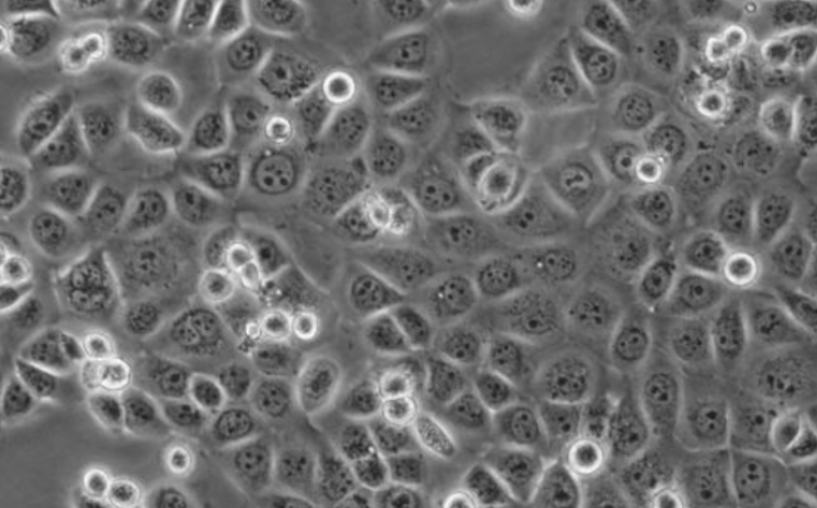

人空白结肠上皮细胞